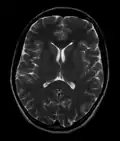

Normal axial T2-weighted MR image of the brain

- T2-weighted (T2W) images: CSF is light, but fat (and thus white matter) is darker than with T1. T2-weighted images are useful for visualizing pathology.[26]